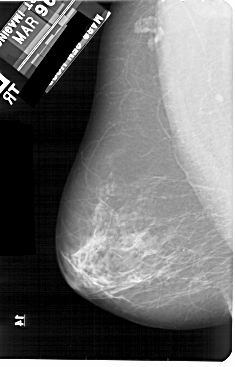

A_1908_1.LEFT_CC

LEFT_CC LINES 5461 PIXELS_PER_LINE 3166 BITS_PER_PIXEL 12 RESOLUTION 43.5 NON_OVERLAY